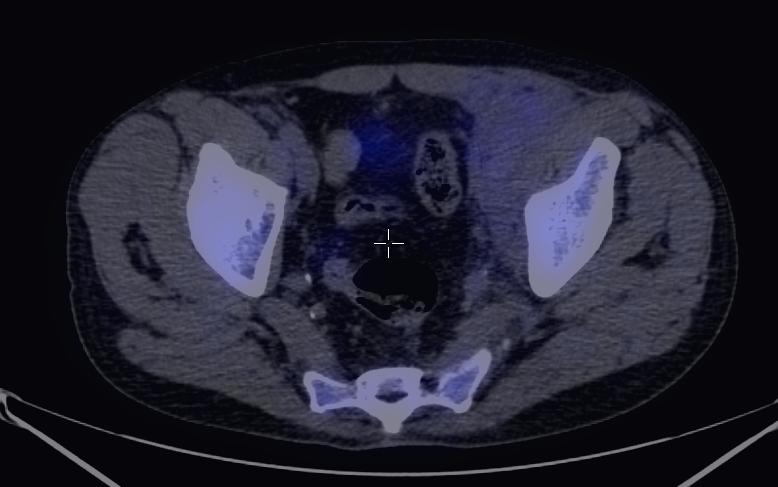

In the early phases of oncologic treatment (so called interim phase) PET examinations seem to be able to differentiate patients that respond well to the therapy, from the ones that are resistant to it. (Figure 12.)

Image

e

f

12. Diffuse large B-cell lymphoma. Neoadjuvant staging (a-c) and after 3 cycles of immuno-chemotherapy, interim (d-f) FDG PET-CT. Maximum Intensity Projection (MIP) PET images (a,d), transversal fusion images (b,e) and CT images (c,f). During staging extended supra- and infradiaphragmatic nodal involvement was found. At the interim examination complete metabolic remission can be seen indicating a good therapeutic response. At the left parailiac region an extensive residual soft tissue mass can still be noted. (e-f).